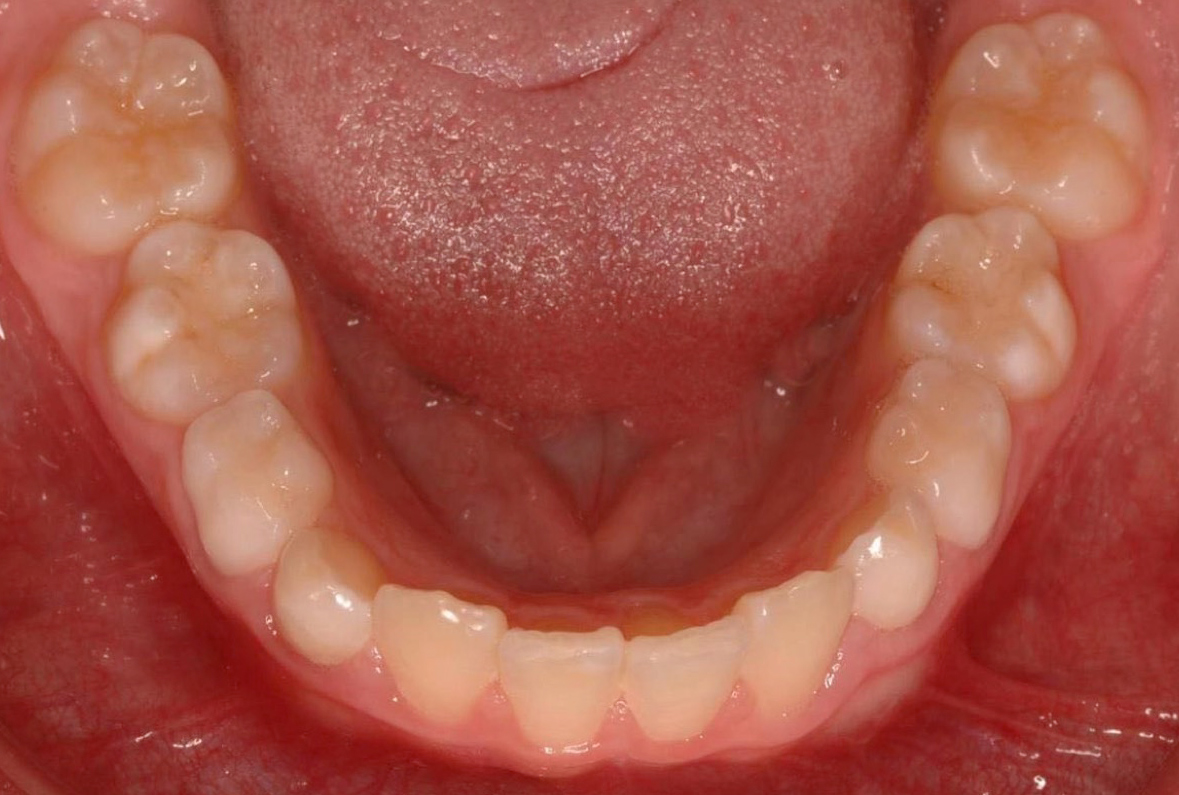

Falta de espacio

Aparece cuando no existe espacio suficiente para que todos los dientes estén alineados juntos en la arcada dentaria.

Puede deberse a un tamaño grande de los dientes, a unas bases óseas estrechas o una mezcla de ambas y los principales signos para identificar este problema serían: dientes apiñados, pérdida prematura de dientes de leche y dientes que erupcionan alejados de su posición normal,